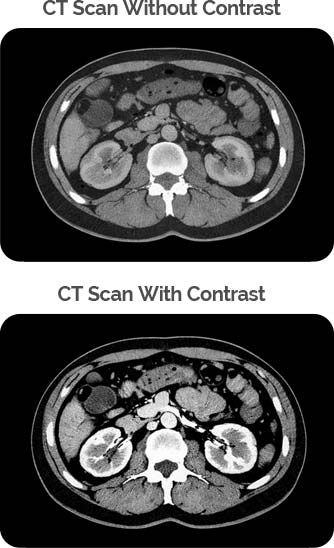

A CT scan (Computed Tomography) is a widely used diagnostic imaging procedure that combines advanced X-ray technology with sophisticated computer processing to generate detailed cross-sectional images of the body. These images provide precise visualization of organs, bones, blood vessels, and soft tissues, supporting accurate evaluation of injury, disease, and structural abnormalities.